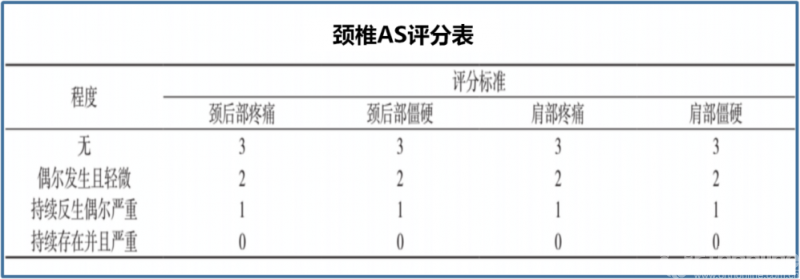

②日本应庆大学(颈椎AS评分表)

为国外较常用量化标准。其按性质分:颈后部疼痛、僵硬和肩部疼痛、僵硬四类;以程度量化:无、偶尔发生且轻微、持续发生偶尔严重、持续存在并且严重;并分别赋予分值:3分、2分、1分、0分。四项相加,共计12分,分值越低越轴性症状越严重。